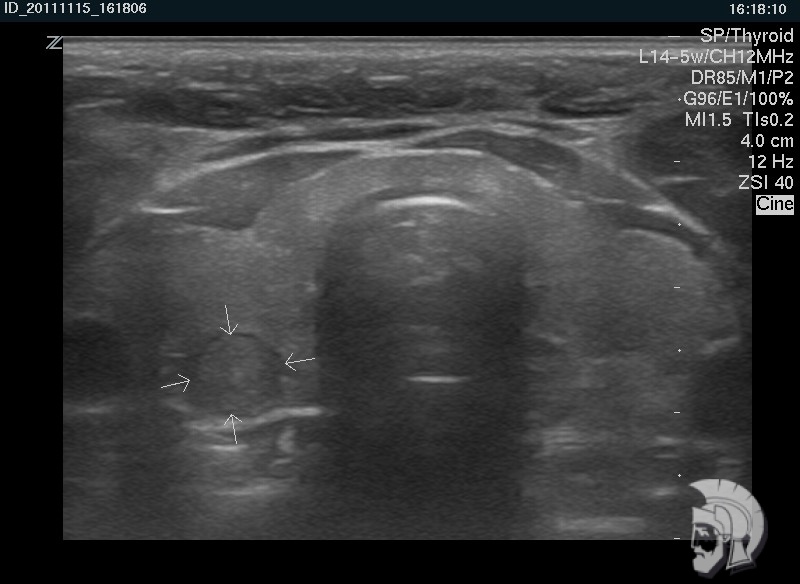

| Фото правостороннего узлового зоба у мужчины 28 лет. Узел в задних отделах правой доли указан стрелками |

|